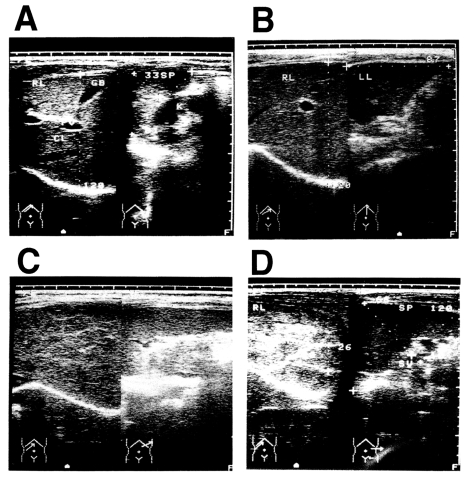

A total of 230 current or former patients with chronic schistosomiasis japonica were examined for liver changes. All patients were from the agricultural village of Beishan, in Yushan county, China, and had their first episode of infection and treatment at least 10 years before this study began. The mean age of the subjects was 52.6 ± 10.5 years and the mean time since their initial treatment was 27.4 ± 8.8 years. Ultrasonographic diagnosis was carried out according to the WHO standard for the diagnosis of liver fibrosis due to schistosomiasis japonica (The Cairo Working Group, 1992; Hatz et al., 1992; Hirayama et al., 1998) (Fig. 1). Ultrasonographic diagnosis determined that there were 44 persons with grade 0 fibrosis, 81 with grade I fibrosis, 99 with grade II fibrosis, and six with grade III fibrosis. The presence of hepatitis B virus (HBV) was not assessed in these patients, but the prevalence of HBV is about 15% in Jiangxi Province (Li et al., 1997). Most of the men in the village smoke tobacco and drink alcoholic beverages, but the women generally do not. The patients had all been treated with praziquantel after each positive faecal examination throughout their lives, but it was not possible to estimate the precise total worm burden of each patient during the clinical course of the disease. Therefore, we tentatively defined an appropriately exposed person as someone with a record of repeated treatments for schistosomiasis japonica over a 10-year period (Hirayama et al., 1998).